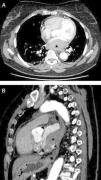

Presentamos el caso de una mujer con dolor centrotorácico opresivo irradiado a la espalda y marcadores miocárdicos positivos, a la que un ecocardiograma detectó una masa en la aurícula izquierda. El hallazgo se confirmó posteriormente con una tomografía computarizada torácica. La semiología en la TC era compatible con un hematoma mural, que se confirmó con una biopsia intraoperatoria.

We present the case of a woman with squeezing mid chest pain irradiating to her shoulder and positive cardiac markers in whom a left atrial mass was identified at echocardiography. This finding was confirmed at chest CT. The signs at chest CT were compatible with a mural hematoma and this diagnosis was confirmed after intraoperative biopsy.